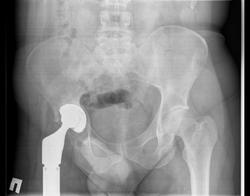

Остеолиз, возникающий на периферийной части эндопротеза в позднем послеоперационном периоде, является основным осложнением тотального замещения тазобедренного сустава у человека и собаки (фото 1).

Исследованию были подвергнуты 5 неразъемных эндопротезов с металл — металлической парой трения (CoCrMo/СоСгМо) по типу К.М. Сиваша Государственного экспериментального предприятия Центрального института травматологии и ортопедии им. Н.Н. Приорова (ГЭП «ЦИТО») и пять разъемных эндопротезов с металлополимерной парой трения (головка — СоСгМо/вертлужный компонент — высокомолекулярный полиэтилен) Швейцарской фирмы MATHYS (фото 2).